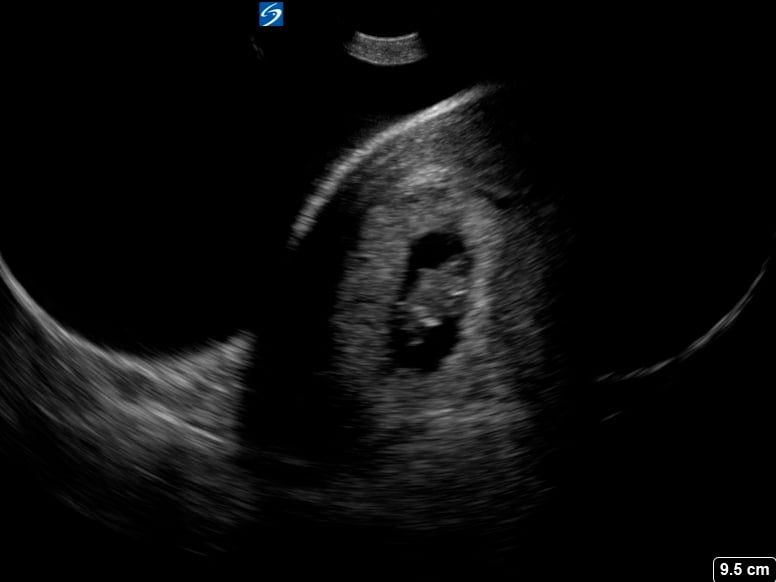

GUSI Video